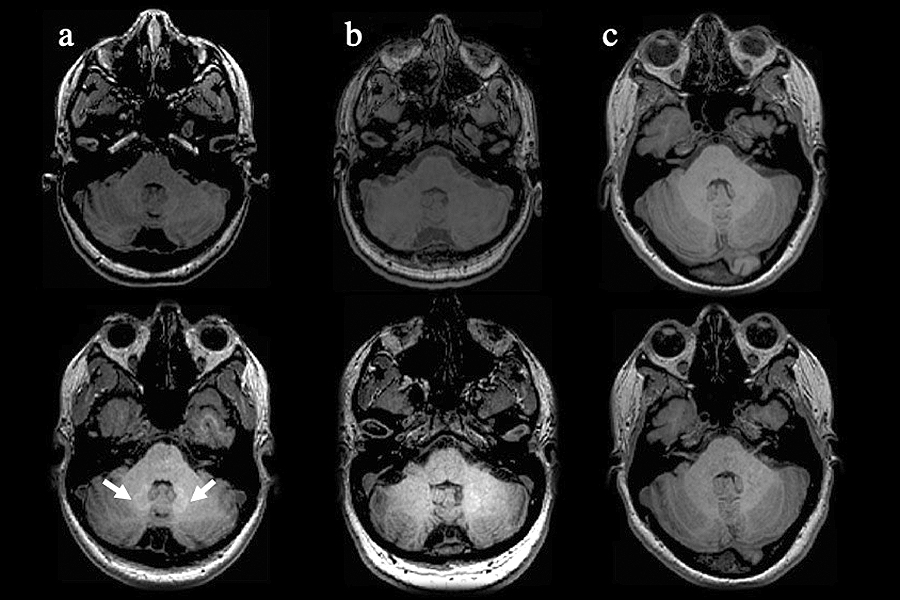

These MRI images of MS patients (a and b) and healthy controls (c) show that patients who had more than 8 scans (a) using gadolinium-based contrast agents have areas of hyperintensity (brighter regions, white arrows) on the scans, indicating gadolinium deposition, compared to the scans of MS patients who had less than 8 scans (b) and healthy controls (c). (Credit: Buffalo Neuroimaging Analysis Center, University at Buffalo)

Of special concern, the UB authors noted, are areas of high intensity within some brain regions that have been identified in patients receiving GBCAs.

“But is it the gadodiamide creating the hyperintensity or is it the disease progression?” The UB study’s main finding was that there was no clear association between GBCA deposition in the brain and development of disease progression.

At the same time, 8.9% of MS patients who received fewer than 5 doses did have hyperintensity in the part of the brain, called the dentate nucleus, involved in voluntary motor function and cognition, which is often affected by MS; none of the healthy controls did.

And while there was no discernible clinical impact, the researchers did find that patients who received more than eight GBCA doses had more brain lesions and more advanced atrophy of grey matter, compared to patients who had fewer than 8 doses.